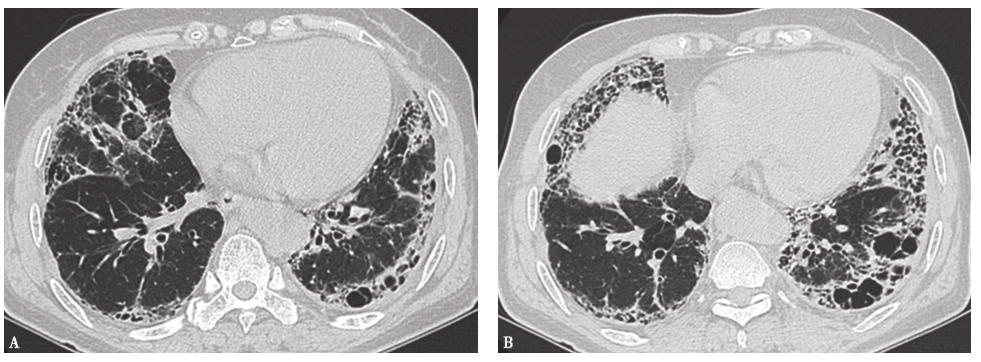

外院胸部CT示两肺散在磨玻璃影、弥漫性小结节影(图1),局部可见牵拉性支气管扩张。

图1外院胸部CT表现

两肺散在磨玻璃影及小结节影(图13),局部网状影,较入院前(图1)明显吸收、好转。